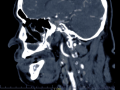

Rozległa torbiel zawiązkowa żuchwy

Paulina Adamska, Maria Mikołajska, Anna Janowska, Anna Starzyńska